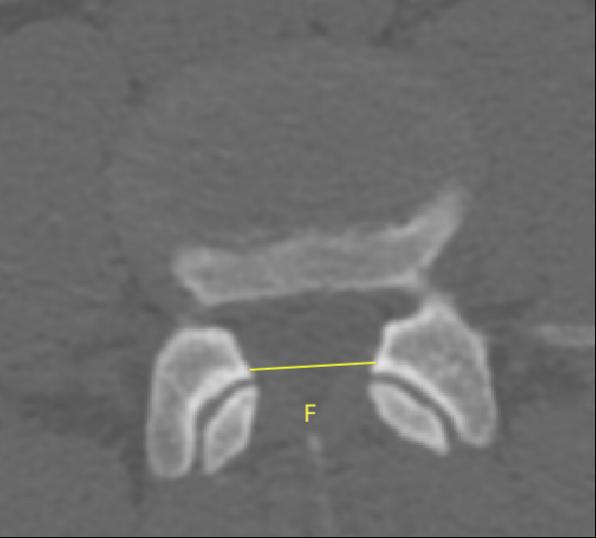

2、通過術前CT測量L4-5節段手術部位的(1)上位椎體后下角水平方向到關節突關節的距離(A);(2)纖維環后緣的中點水平方向到關節突關節的距離(B);(3)下位椎體后上角水平到關節突的距離(C);(4)上位椎體的椎弓下切跡與下位椎體椎弓上切跡連線的距離(D),圖 6;(5)在手術節段的棘突矢狀位CT層測量椎間隙高度(E),圖 7;(6)在手術節段的關節突關節橫截面CT層測量關節突間距離(F),圖 8,再通過術中及術后CT判斷患者椎間孔成型級別,將A-F測量數據與5級成型中的各級別成型進行相關性分析。

圖 8 F的測量方式 |